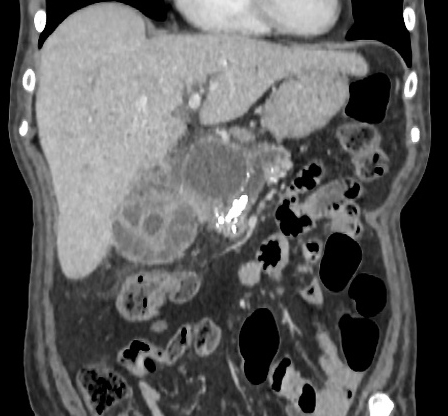

Cholecystite

lithiasique aigue : Vesicule biliaire est distendue

, image epaissisement et rehaussement hyperdense de la paroi

avec epanchement perivesiculaire . La lithiase

hyperdense situe a infundibulum . Image

radiologique TDM + contrast en coupe axiale |